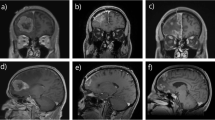

RN is a complication of high dose radiation (used in SRS), which results in the permanent death of irradiated brain tissue. Aside from dose, RN has also been significantly correlated with larger target volumes by several studies [43,44,45]. Resection cavities often remodel unpredictably during the time intervals between surgery, SRS planning, and SRS administration, making it challenging to derive an accurate clinical target volume (CTV) and leaving much variability in clinician practice [46,47,48]. Current consensus contouring guidelines for a clinical target volume include contouring the entire surgical tract (regardless of tumor location), extending the CTV 5–10 mm along the dura overlying the bone flap, and adding 5 mm margin into the adjacent sinus when preoperative venous sinus contact was present [48]. Such a large volume of irradiation leaves parenchymal tissue easily vulnerable to radiotoxicity. The use of hypofractionated post-op SRS (HSRT) appears to be one strategy used recently to reduce the rates of RN for large surgical cavities. nSRS may reduce morbidity associated with RN because the target volume is easily interpretable in scans and therefore, contoured without much interpretation, leaving less tissue irradiated. Furthermore, during surgery, any irradiated rim of healthy tissue is usually removed, resulting in less injured tissue and lower cytokine concentrations required to catalyze RN [14, 19, 33, 49]. Figure 2 shows a treatment planned target volume contour for a patient treated with nSRS and Fig. 3 overlays a mock planned target volume contour (with an additional 1 mm. margin) over the post-operative cavity; these figures illustrate the advantages of nSRS in planning and treatment.

Left temporal post-operative cavity (blue) with an added 1 mm. margin (pink) and mock Gamma Knife plan (yellow; 27 Gy prescription dose, 3 fractions) based on the T1 post contrast MRI images in the coronal a, transverse b, and sagittal c views. This patient was treated with neo-adjuvant SRS prior to surgical resection and is the same patient in Fig. 2